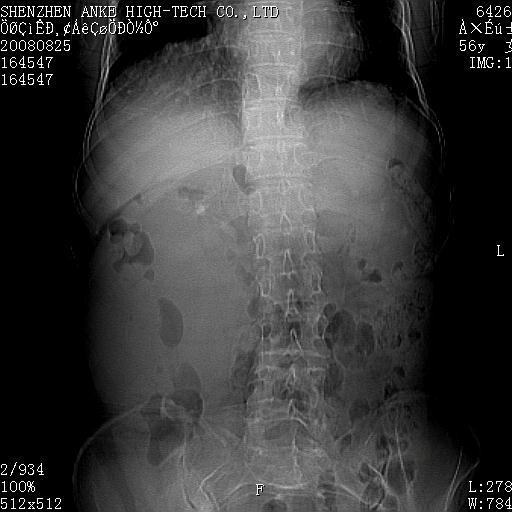

患者,女性,56岁,腰痛3年,查:右腹部约8x10cm肿块,固定,无压痛;8月23日在外院做了平扫,发现右肾巨大肿块(外院具体诊断不祥);今天在我院做了静脉肾盂造影,示:右肾明显增大,分泌功能明显减弱。

右肾癌可能大。

右肾癌

右肾癌可能性大.

右肾占位、癌可能性大。

支持右巨大肾癌。

1)考虑右肾癌并右肾静脉瘤栓形成。2)脂肪肝。

右肾癌可能性大。

右肾癌性变。

考虑右肾癌可能性。